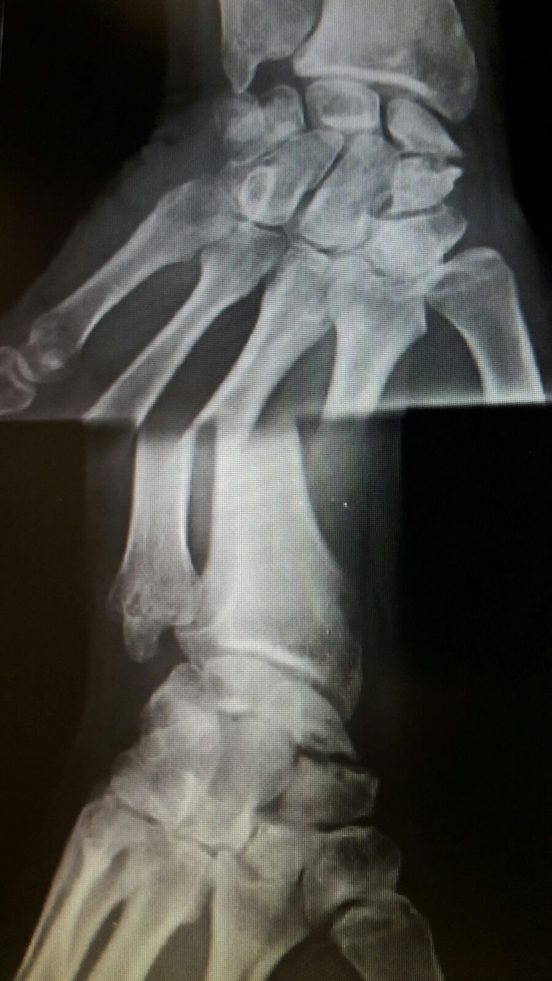

Fractura antigua de escafoides